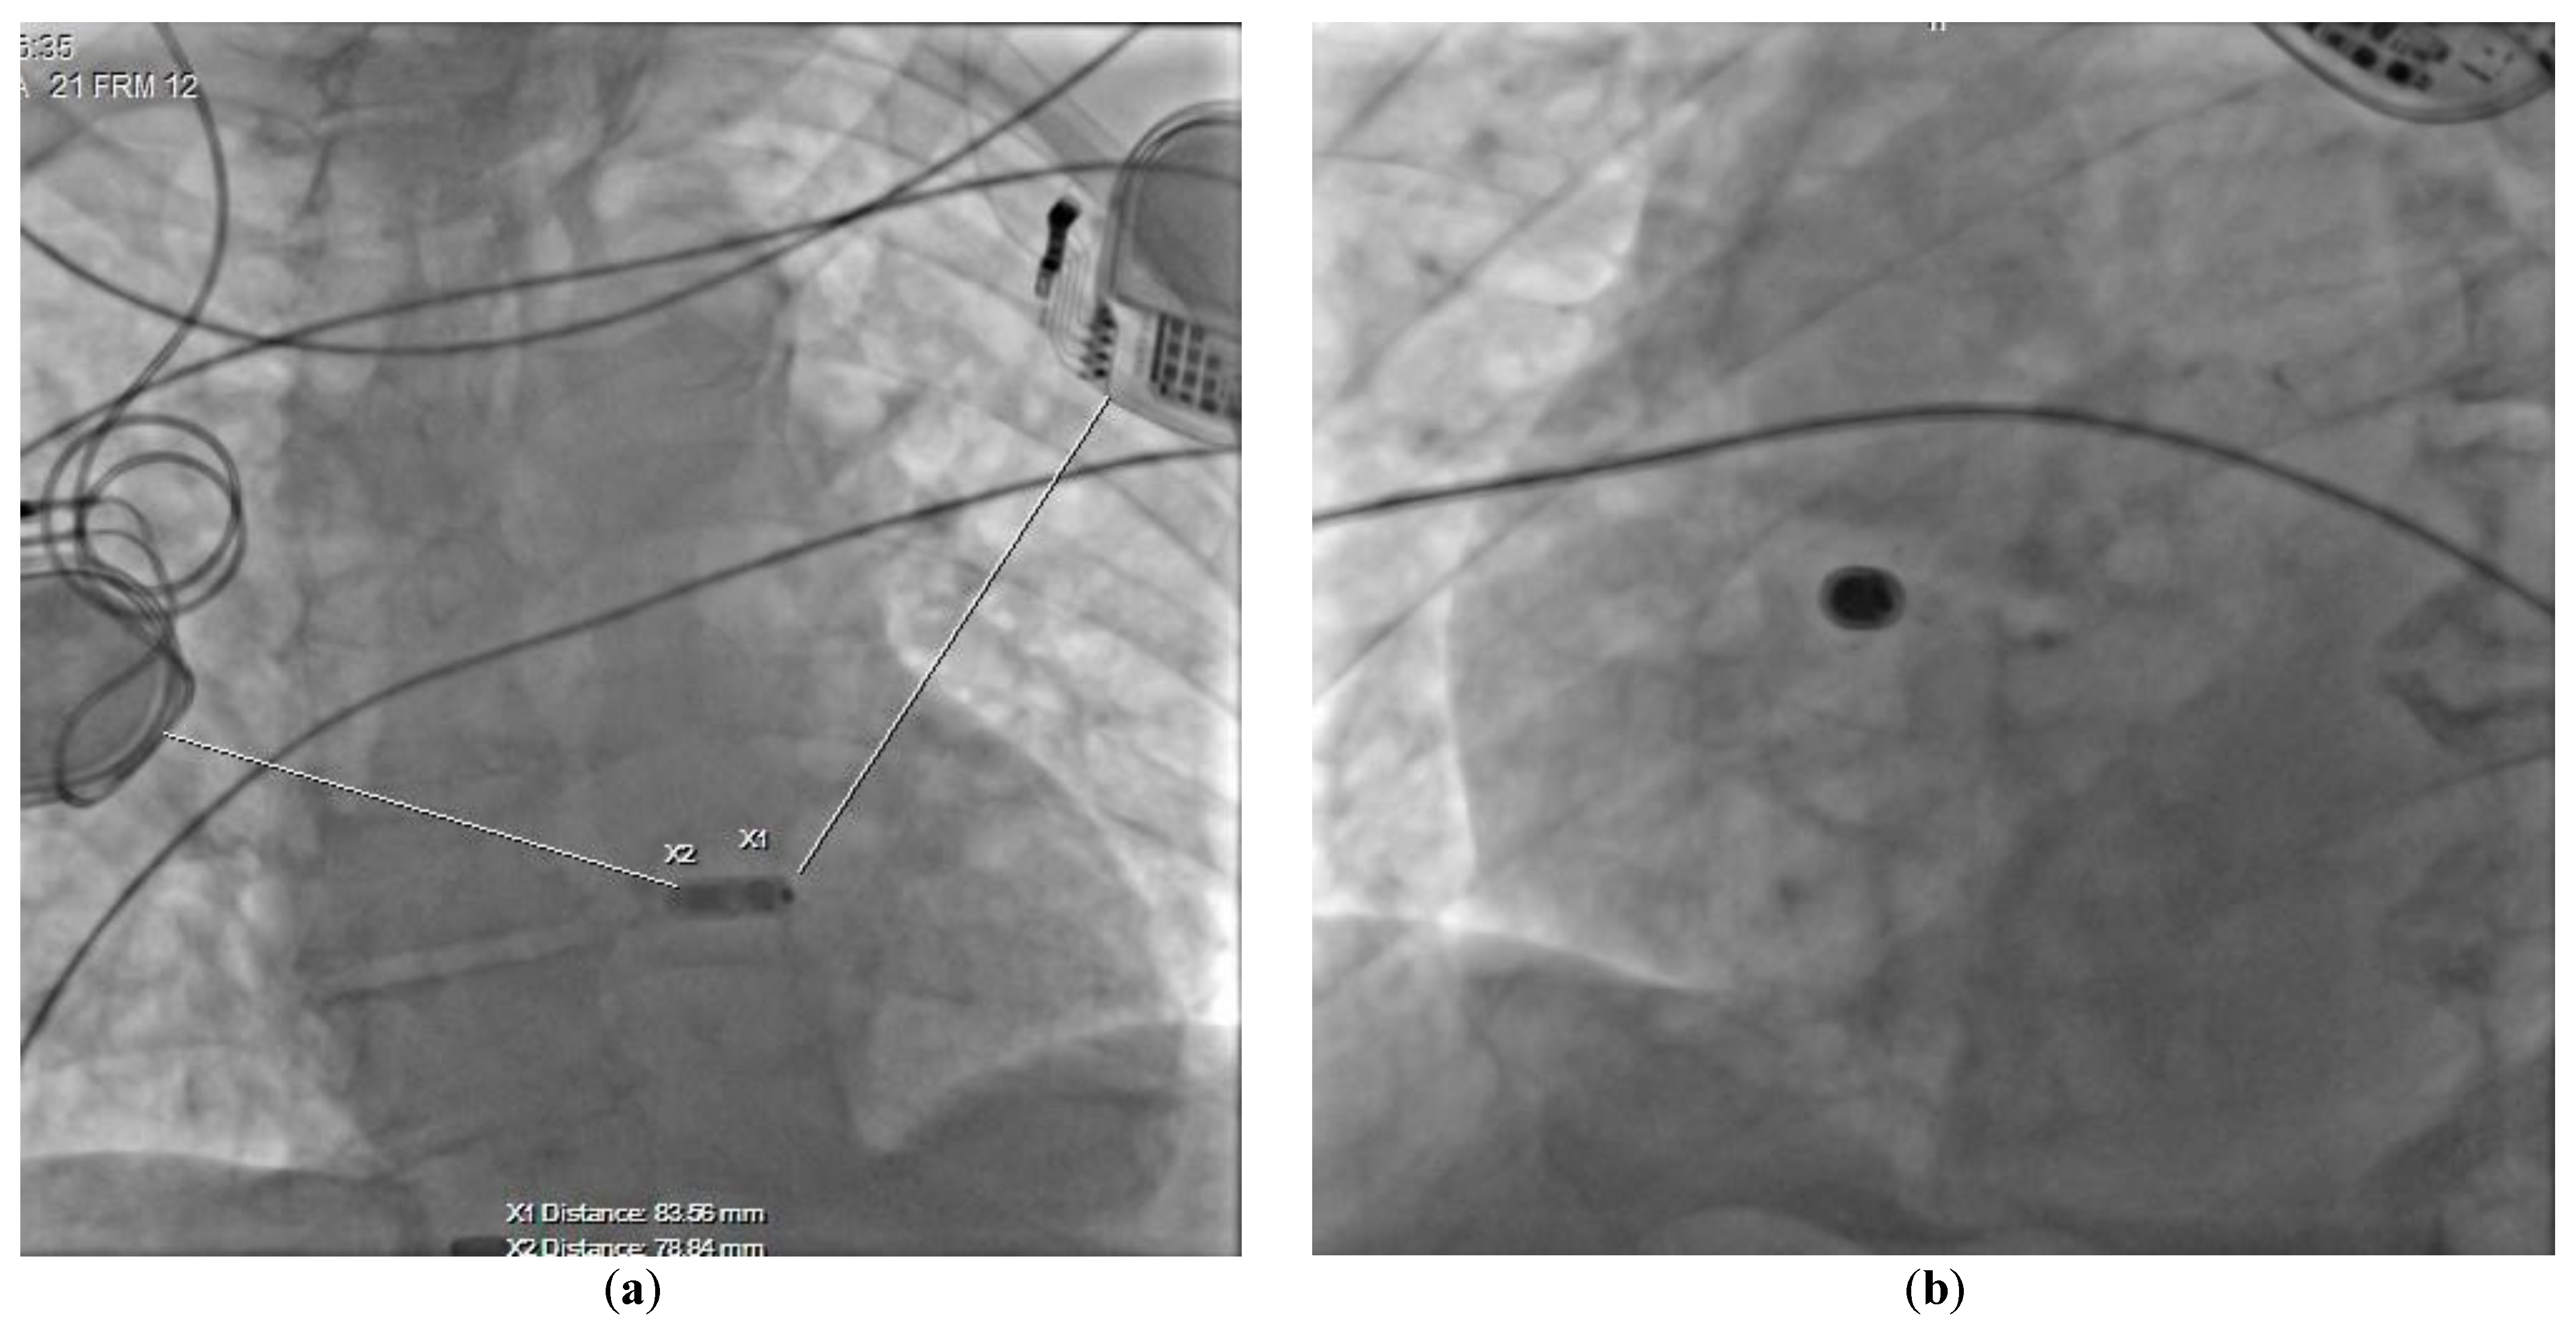

At the time of admission to the Cardiology Department, the patient was in a good general condition. Echocardiography confirmed a severe aortic stenosis and revealed that his left ventricular ejection fraction was normal. The valve disease might also have been considered as a reason for syncope, however, the ECG clearly indicated that the patient primarily required a cardiac PM implantation as per the ESC 2021 guidelines class I recommendation [4]. We had a few options to minimize the risk of interferences, including the usage of epicardial leads, but after a discussion with a patient, we decided to implant a leadless AV pacemaker (LPM; Micra AV MC1AVR1, Medtronic). The LPM implantation was performed in the electrophysiology laboratory with the participation of a neurosurgeon, who turned off both DBS generators before the procedure. The LPM was implanted in the mid-septum of the right ventricle via the femoral vein access. The atrioventricular synchronous cardiac pacing was confirmed (Figure 1b) and the tests showed correct pacing threshold, ventricular sensing as well as impedance (0.25 V/0.24 ms; >20.0 mV; 920 ohms; respectively). Then, the DBS generators were turned back on and optimally programmed. We did not record any significant interference by DBS on LPM, although they were placed at a closer than recommended distance one from another (Figure 2).

Figure 2. Chest radiogram presenting the final position of the implanted device in (a) AP, and (b) LAO 32° projections.